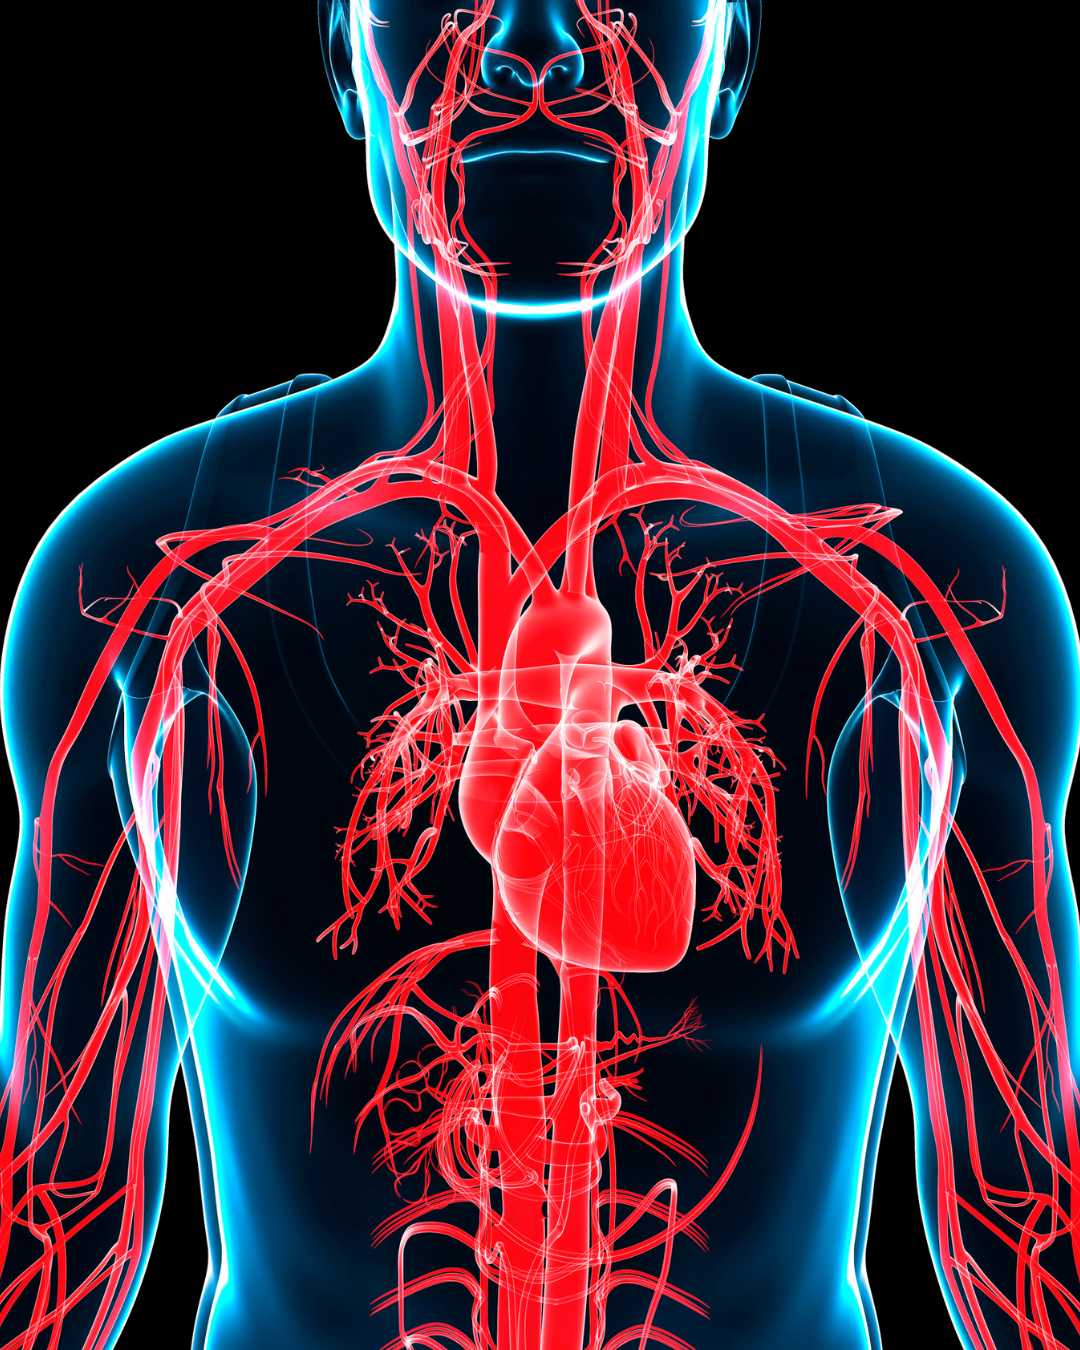

Moni tietää, että ylipaino lisää sydän- ja verisuonitautien riskiä. Mutta harva ymmärtää, että liikapaino voi vaikuttaa suoraan sydänlihaksen rakenteeseen – ja jopa aiheuttaa äkkikuoleman. Tuore suomalaistutkimus paljastaa karun totuuden: rasva voi kertyä suoraan sydämen sisälle, heikentäen sen toimintaa ja altistaen hengenvaarallisille rytmihäiriöille.

Professori Juhani Junttilan johtama tutkimusryhmä Oulun yliopistollisessa sairaalassa löysi merkittäviä määriä rasvaa sydänlihaskudoksesta ihmisiltä, jotka olivat kuolleet äkillisesti. Tämä ei ole normaalia – sydämessä ei pitäisi olla lainkaan rasvaa.

Toisin kuin sidekudos, rasva ei johda sähköä eikä osallistu sydämen pumppaustoimintaan. Sen sijaan se häiritsee sydämen toimintaa, erittää tulehdusta ylläpitäviä aineita ja luo alustan kohtalokkaille rytmihäiriöille.

Puolet sydänperäisistä kuolemista on äkillisiä, ja usein ne tapahtuvat täysin yllättäen ilman aikaisempia oireita. Äkkikuolema onkin monelle ensimmäinen – ja viimeinen – merkki piilevästä sydänsairaudesta. Ylipaino ei ole vain ulkonäköasia – se on hengenvaarallinen.